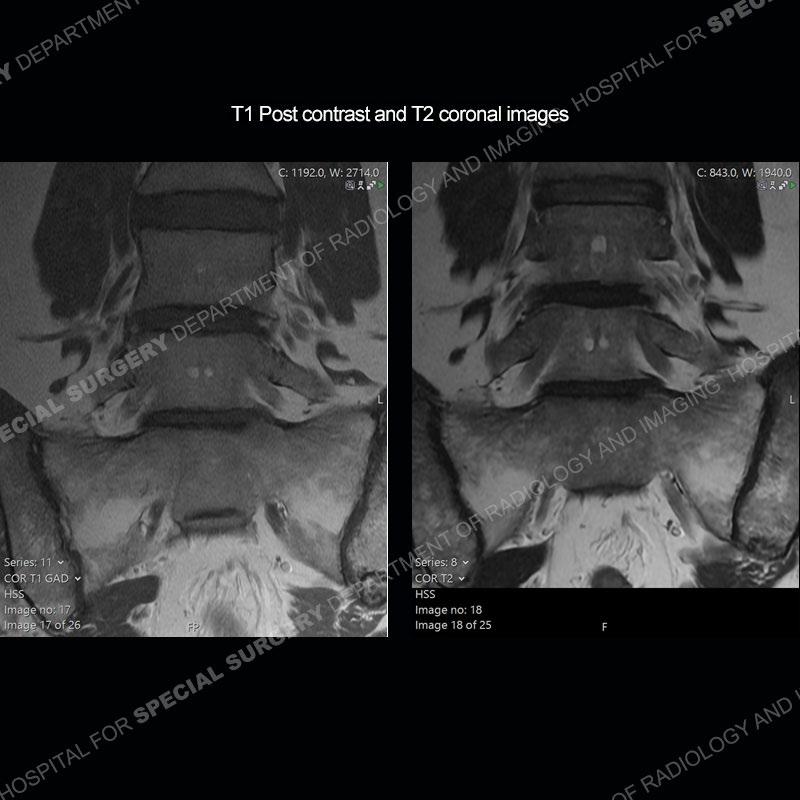

Post operative changes are seen on the left side at L5-S1 where there is near complete removal of the left sided L5 lamina, partial resection of the left L5-S1 facet joint, and resection of the left sided ligamentum flavum. In the anterolateral epidural space about the subarticular recess is a mass that demonstrates similar T1 and T2 signal characteristics to the adjacent degenerated disc. There is enhancement about the periphery of the mass, but the majority of this somewhat geographic or polyploid mass demonstrates no enhancement. The mass exerts prominent mass effect on the left S1 axillary sleeve/proximal nerve root. The left S1 nerve root shows enlargement and increased enhancement as compared to the contralateral right side.

Diagnosis: Recurrent Disc Herniation

Not as much of a diagnostic dilemma as some other cases but more so just a very nice example of what can be a difficult assessment at times. The evaluation of granulation tissue/scar/epidural fibrosis vs. disc herniation particularly in the earlier post operative period can be very difficult. Clues that can assist in identifying a disc herniation are a more geographic or polypoid nature to the mass, signal characteristics similar to the adjacent degenerated disc, mass effect upon the thecal sac/adjacent neural structures, and a typical enhancement pattern. As the disc material is avascular, as long as imaging is performed in a relatively rapid fashion after contrast administration (within 20-30 minutes), the granulation tissue around the disc will enhance but the disc material itself will not. If there is a marked delay between contrast administration and imaging, there may be diffusion of contrast into the disc making the assessment very difficult. The marked utility of contrast to help delineate disc vs. scar has led to our institution employing contrast fairly uniformly within the first two years following surgery.